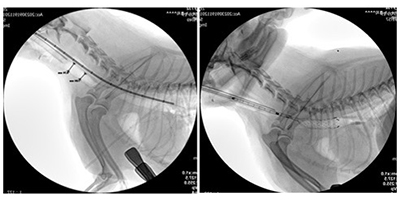

1. 폐동맥협착증

폐동맥 협착증은 폐동맥 판막이 좁아져 심장에서 폐로 향하는 혈류에 장애가 발생하는 질환입니다. 중등도 이상의 협착이 확인되는 경우 풍선판막성형술을 통해 좁아진 판막을 확장하여 혈류 흐름을 개선합니다. 풍선판막성형술은 목정맥 또는 대퇴정맥을 통해 카테터를 삽입한 뒤, 협착이 발생한 폐동맥 판막 부위까지 기구를 정밀하게 접근시키는 방식으로 진행됩니다. 이후 풍선을 확장하여 좁아진 판막을 물리적으로 넓혀주며, 판막을 통과하는 혈류 속도를 낮추고 심장과 폐 사이의 압력 경사를 완화하는 것을 목표로 합니다.

시술이 성공적으로 이루어질 경우 우심실의 압력이 감소하고 폐로 향하는 혈류 흐름이 개선될 수 있습니다. 이에 따라 운동불내성이나 실신과 같은 임상 증상이 완화되며, 장기적으로는 우심부전으로의 진행을 늦추는 데 도움을 줄 수 있습니다.

폐동맥협착증 풍선확장술 시술 이미지

시술 이미지